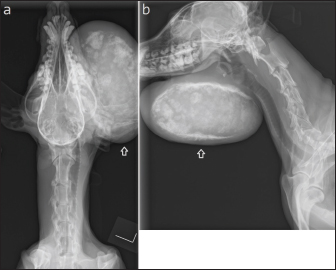

Case 1 is a 14-year-old, unneutered male miniature pinscher weighing 6.7 kg. For over 5 years, the patient had repeatedly been diagnosed with salivary gland cysts at several hospitals due to the presence of mucus accumulation in the mandible. He had been routinely treated medically by aspirate removal. Three months before first visiting the university, mucus viscosity decreased and became partially indurated, leading to an increase in the frequency of puncture removal. One month earlier, the mucus in the reservoir had solidified, making it impossible to aspirate. As such, the patient was referred to our hospital for further examination and treatment. The size of the mandibular mass lesion at the time of the first visit (day 1) was 130 * 98 * 75 mm (Figs. 1 and 2). Blood tests showed hypoalbuminemia (Table 1).

Fig. 2. X-ray examination of the skull. Calcification was seen inside the mass lesion that increased from the mandible to the neck (arrow). (a) AP, anterior-posterior view and (b) LR, right lateral view.

On imaging examination, the typical case of extraskeletal osteosarcoma is a soft-tissue mass with localized sclerosis and no lesion in the adjacent bone (Schena et al., 1989). In the present report, the mass lesion and the adjacent mandible in this case were consistent with this finding on both X-ray and CT. Together with the histopathological examination, these were some of the determining factors in diagnosing extraskeletal osteosarcoma in this case. Extraskeletal osteosarcoma may be considered a differential diagnosis in soft tissue mass lesions with sclerosis in the submandibular region in the absence of an adjacent mandible or other bone lesions. Unfortunately, there were no clear histologic findings that the extra salivary osteosarcoma in this case is of salivary gland origin.